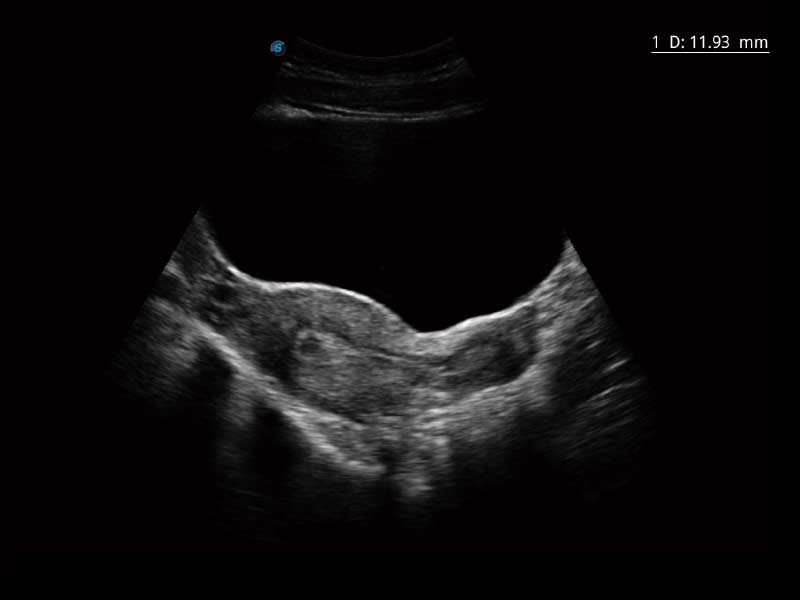

PW自动包络分析,对血流动力学指数快速测量,自动生成结果,同时也支持可编辑的手动包络功能,对感兴趣区域进行单独分析,提高诊断准确率。